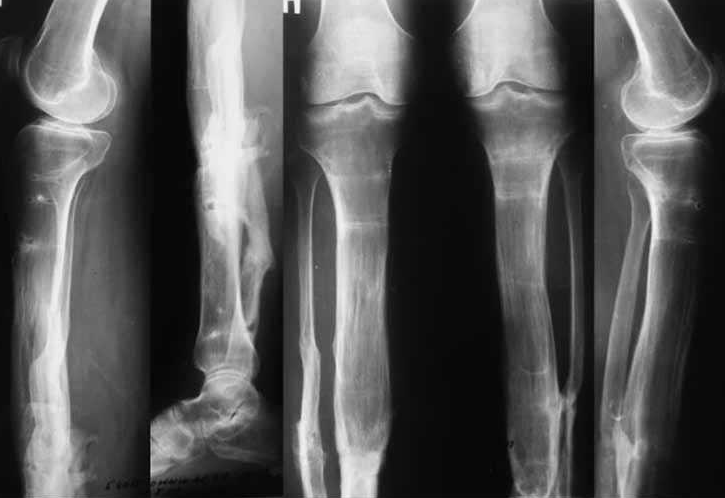

Любого доктора можно быстро подготовить как рентгенлаборанта и дать необходимые знания для оценки рентгенограмм.

Изучение проблемы низкого качества рентгенограмм на Вашем оборудовании.